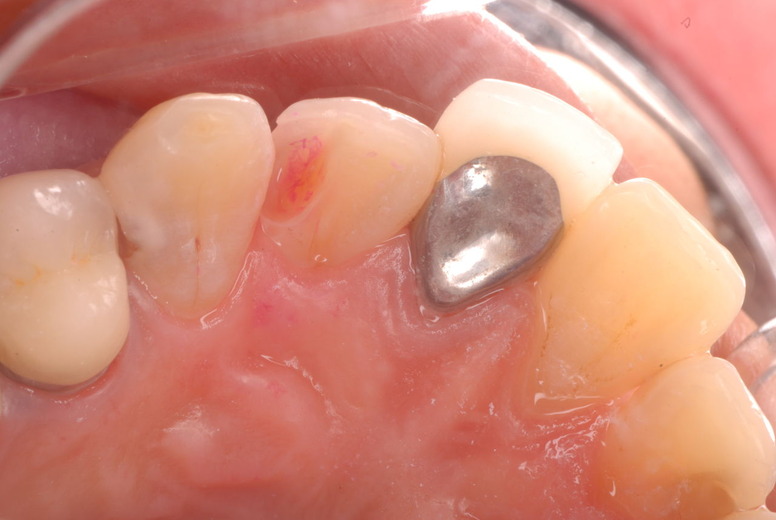

色々不満な入れ歯です。

発音や見える金属が気になるようです。

入れ歯の話から入りました。色々不満で注文があるようです。でも話が一段落して口腔内を調べると殆どの歯が重症で抜けそうな歯だらけなのです。

なぜ病気になるのかわからない方が多すぎます。歯が抜けるのは病気だからです。病気を治さずに何かお口の中に入れても土台である歯が抜けてしまっては同じことなのです。